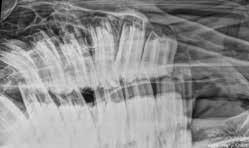

Daniel BoudrenghienDans un article précédent, le développement des dents et l’usure de celles-ci au cours de la vie du cheval nous avait conduit à déterminer trois catégories d’âge. Chacune d’entre elles était liée à une conformation et à des particularités propres de la dentition. Ainsi, on peut distinguer la première catégorie, le jeune cheval, de 0 à 5 ans ; ensuite l’adulte de 5 à 17 ans et enfin le senior après 17 ans. En effet, les pathologies dentaires gériatriques s’observent déjà à partir de 17 ans chez les chevaux. Nous allons ici nous intéresser à la première catégorie d’âge et à ses pathologies spécifiques.

Les pathologies du jeune cheval sont liées au désordre du développement et de l’éruption des dents ainsi qu’aux anomalies du développement crânio facial. Dans les anomalies du dévelop pement crâniofaciale, la plus fréquente est la brachygnathie (mâchoire inférieure plus courte), la prognathie (mâchoire supérieure plus courte) est elle plus rare. La plus impressionnante reste sans aucun doute le Wry Nose ou campy lorrhinis lateralis qui consiste en une déviation de la mâchoire inférieure par rapport à la supérieure. Le diagnostic de toutes ces pathologies est facile à réaliser en levant les lèvres du poulain et en observant. Elles peuvent donc être détectées et prises en charge de façon précoce. Leur traitement reste chirur gical.

Les désordres du développement dentaire constituent un autre groupe de pathologies qui affecte régulièrement les jeunes chevaux. On y distingue les dents surnuméraires. Elles affectent tout type de dent allant des incisives en passant par les canines, les prémolaires et les molaires. Ces dents surnuméraires dans la majorité des cas entrainent un déplacement et une position incor recte des autres dents voisines créant alors un espace entre elles (diastèmes) dans lequel les aliments vont s’accu muler, provoquant de la gingivite puis de la périodontite. C’est une situation très inconfortable pour le cheval qui en souffre. Cette situation, si elle n’est pas prise en charge, peut aboutir à une extraction de la ou des dents impliquées.

Un autre désordre du développement dentaire est la dysplasie et consiste en une anomalie structurelle de la dent elle-même, soit au niveau de la pulpe (nombre de chambres pulpaires anormale), soit au niveau de la compo sition des éléments constituant la dent (émail, dentine, cément). Ce type d’ano malie entraine souvent des problèmes apicaux qui se soldent par une extraction.

La rétention des dents déciduales (dents de lait) est un autre désordre du développement qui lui aussi peut être lourd de conséquences. La persis tance de dents de lait peut entrainer des défauts de positionnement des dents définitives au moment de leur éruption. Elle peut également empêcher l’éruption correcte de la dent définitive. Certaines dents définitives sont alors impactées et une réaction de l’os de la mâchoire ou du chanfrein peut apparaître. Ce sont les kystes d’éruption, bumps en anglais. Ceux-ci peuvent être accompagnés d’un écoulement lorsque la dent impliquée est impactée verticalement.

La dernière pathologie qui fait partie des désordres du développement et que nous aborderons dans cet article est le déplacement des dents au moment de l’éruption. Les incisives et les mâche lières (prémolaires et molaires) sont surtout concernées. Elles peuvent être déplacées par manque de place si une dent surnuméraire est présente mais elles peuvent également être le siège d’un défaut de positionnement lors de leur éruption. Les dents entreprises dans ces deux phénomènes pathologiques peuvent être le siège d’excroissance sur la surface occlusale car elles sont le siège d’une usure tout à fait anormale. Elles sont aussi souvent impliquées dans la formation de diastèmes (espace entre les dents) qui doivent alors être nettoyés ainsi que les poches parodontales qui les accompagnent, élargis mécani quement et traités à l’aide de techniques permettant la cicatrisation de la gencive qui est enflammée. Les excroissances peuvent être éliminées à l’aide de matériel électrique.

En conclusion, le nombre de patho logies liées au jeune âge du cheval nécessite d’une part un diagnostic précoce et d’autre part une prise en charge rapide car la majorité de ces problèmes dentaires, s’ils sont traités de façon adéquate, peuvent rentrer dans l’ordre et ne plus être préjudiciables pour le reste de la carrière du cheval. Un examen visuel dans les six premiers mois de vie du poulain devrait donc être envisagé pour pouvoir exclure les problèmes de développement. Ensuite un examen tout les 6 mois de 2 à 5 ans permet de gérer la cohabitation entre les dents de lait et les dents définitives jusqu’à ce que le cheval dispose de sa dentition complète d’adulte. La gestion anticipative des pathologies d’éruption

permet comme en médecine humaine d’éviter au maximum les extractions prématurées.

Fig. 1,2,3 Brachygnathie et correction chirurgicale par la pose d’un cerclage bloquant la mâchoire la plus longue Fig. 4 Wry Nose

Fig. 5 Prémolaire surnuméraire Fig. 6 Anomalie d’éruption

Fig. 7 Anomalie de positionnement des incisives due à une dent surnuméraire Fig. 8 Persistance des incisives de lait Fig. 9 Kystes d’éruption suite à une impaction de la première molaire

Fig. 10 Déplacement d’une prémolaire inférieure